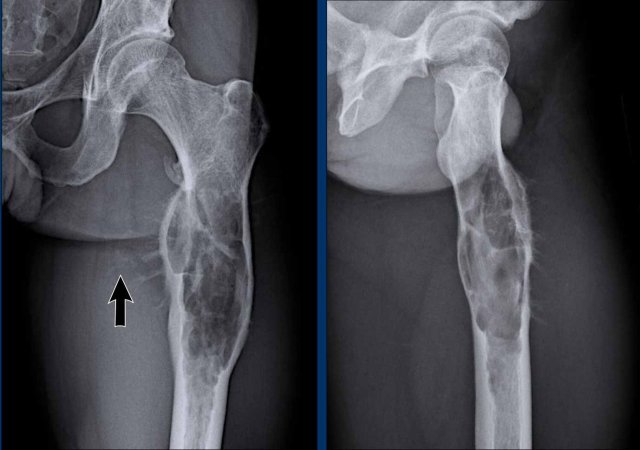

Images

Radiographs demonstrate an

aggressive expansile osteolytic lesion in the proximal femur diaphysis of a 30-year-old patient.

There

is extensive cortical scalloping and a spiculated, hair-on-end periosteal

reaction.

Note the pathological fracture of the trochanter minor.

There is subtle mineralization in the soft

tissues medially (arrow).

Conclusion

All these findings are pointing

towards a malignant bone tumor.

In the differential diagnosis (taking

into account the age and diaphyseal location) we would include a Ewing sarcoma,

but also a high grade chondrosarcoma.

Although Langerhans cell

histiocytosis may also present in the diaphysis of a long bone in this age

group, this tumor is very large and the periosteal reaction is too

aggressive.

Continue with the MRI…

MRI confirms the T2

hyperintense multinodular aspect of a chondroid tumor.

There is a large soft

tissue mass present anteromedially. There is marked periostitis on MRI, bone

marrow oedema proximally and surrounding oedema in the soft tissues.

Note the septonodular

enhancement pattern.

There is no enhancement

cranially in the tumor and in the soft tissue mass. This is regarded as a mucoid

component.

Based on the MRI findings, we should make the diagnosis of a chondrosarcoma grade II or higher.

Treatment was wide resection.

Pathology diagnosis: Chondrosarcoma grade III

A mucoid component is one feature of a high grade chondrosarcoma, visible for both radiologist and pathologist.

The pathologist also assesses cellularity, nuclear atypia and mitoses in the tumor, which are higher than in ACT or grade I chondrosarcoma.